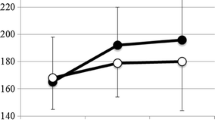

Radiographic outcomes

The Cobb angle of the primary cases changed from mean 65° ± 13° preoperatively to 28° ± 12° postoperatively (55% reduction). The mean frontal Cobb angle of the conversion cases was 64° ± 11° at fist surgery and 38° ± 9° at conversion. This curve was reduced considerably less as expected to 35° ± 6° (Table 2). For all cases (primary and conversions) reduction from initial until after conversion was 59° ± 17° to 30° ± 11° (Table 3). This angle slightly increased to 37° ± 12° at latest follow-up, p < 0.001 (95% CI 3.3–10.3) (Fig. 5). Individual demographics for every patient are visible in Table 2. Rotation of the apical vertebra improved from mean 27° ± 8° to 20° ± 9° postoperatively, but was partially lost to 23° ± 9° during follow-up, p = 0.261 (95% CI − 2.5–8.6). Kyphosis and lordosis both increased by an average of 5° during follow-up (Table 3). T1–S1 height increased from average 337 ± 31 mm postoperatively to 361 ± 39 mm at last follow-up, p < 0.001 (95% CI 13.5–33.3) (Fig. 6). Spinal T1–S1 growth rate averaged 10 mm/year over 3 years until last follow-up (Table 4). There was no difference in growth rate between conversion and primary cases (Table 2). None of the patients reached the maximum distraction point of the rod during follow-up.